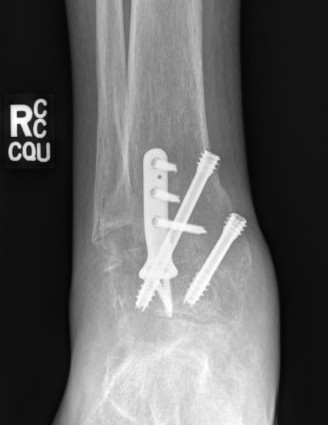

Fixation

- position foot, check with image intensifier

- +/- bone graft

- two cannulated screws from medial tibia to talus dome / neck

- +/- screw medial malleolus to talus

- +/- screw fixation fibular / onlay graft